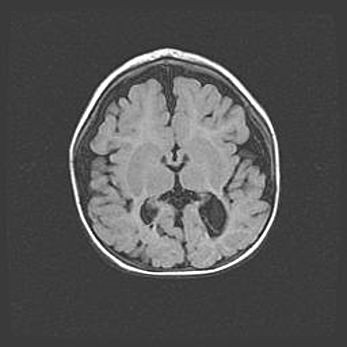

Сообщающаяся гидроцефалия. Кистозная энцефаломаляция головного мозга.

Возраст: 3 месяца 4 дня

Вес: 3100 г

Пол: женский

Окружность головы: 34 см

Срок гестации: 31 неделя

Кистозная энцефаломаляция головного мозга - одна из форм поражения головного мозга в детском возрасте. Характеризуется возникновением множественных и распространённых кист в коре, белом веществе и подкорковых образованиях головного мозга у плодов, новорождённых и детей раннего возраста. Развитие кистозной энцефаломаляции связано с внутриутробной асфиксией и гипотонией, родовой травмой, тромбозом синусов, пороками развития сосудов, инфекциями, сепсисом и другими причинами. Наиболее значимые инфекционные агенты: вирусы простого герпеса, цитомегалии, краснухи, токсоплазмы, энтеробактерии, золотистый стафилококк и другие.